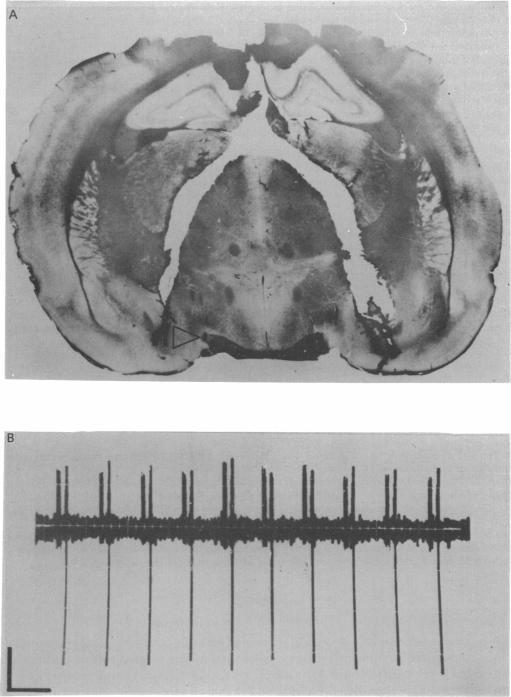

1. Recordings were made from a total of fifty-three neurones in the supraoptic nuclei of four groups of rats: intact rats, animals in which the hypothalamus had been partly denervated by anteriorly or posteriorly placed semicircular cuts, and rats with a totally deafferented hypothalamus. 2. When first encountered, cells from intact animals fired at a mean rate of 5.08 +/- 0.78 spikes/sec, those from posteriorly isolated hypothalami at 3.93 +/- 0.63 spikes/sec, those from the anteriorly isolated hypothalami at 2.05 +/- 0.83 spikes/sec, and those from totally isolated hypothalami at 0.99 +/- 0.46 spikes/sec. 3. When stimulated osmotically by an intraperitoneal injection of ml. 1.5 M-NaCl, eight out of eight cells in intact rats showed a significant increase in firing rate between 20 and 30 min after the injection. Six out of nine cells in posteriorly isolated hypothalami showed significant but smaller responses. No increase in firing rate could be detected in seven cells from totally isolated hypothalami or from eight cells in hypothalami partly isolated by anterior cuts. 4. The results imply that under the conditions of these experiments by the spontaneous activity of the supraoptic nucleus in intact animals was maintained by an extrahypothalamic excitatory input, that partial hypothalamic isolation reduced its intensity, possibly by unmasking an inhibitory input, and that total isolation reduced it to an even greater extent. Osmotic activation of supraoptic cells was only possible when the anterior connexions of the hypothalamus were intact. Thus the cerebral osmo-receptors for vasopressin release may be situated outside the supraoptic nuclei.

1. 对四组大鼠视上核中的总共53个神经元进行了记录:完整大鼠、下丘脑通过前侧或后侧半圆形切口部分去神经支配的动物以及下丘脑完全去传入的大鼠。2. 首次记录时,完整动物的细胞平均放电频率为5.08±0.78次/秒,后侧分离下丘脑的细胞为3.93±0.63次/秒,前侧分离下丘脑的细胞为2.05±0.83次/秒,完全分离下丘脑的细胞为0.99±0.46次/秒。3. 通过腹腔注射1.5 M - NaCl进行渗透压刺激时,完整大鼠的8个细胞中有8个在注射后20至30分钟内放电频率显著增加。后侧分离下丘脑的9个细胞中有6个显示出显著但较小的反应。完全分离下丘脑的7个细胞或前侧切口部分分离下丘脑的8个细胞中未检测到放电频率增加。4. 结果表明,在这些实验条件下,完整动物视上核的自发活动由下丘脑外兴奋性输入维持,下丘脑部分分离可能通过揭示抑制性输入降低了其强度,而完全分离则使其降低到更大程度。只有当下丘脑的前侧连接完整时,视上细胞的渗透压激活才有可能。因此,血管加压素释放的脑渗透压感受器可能位于视上核之外。